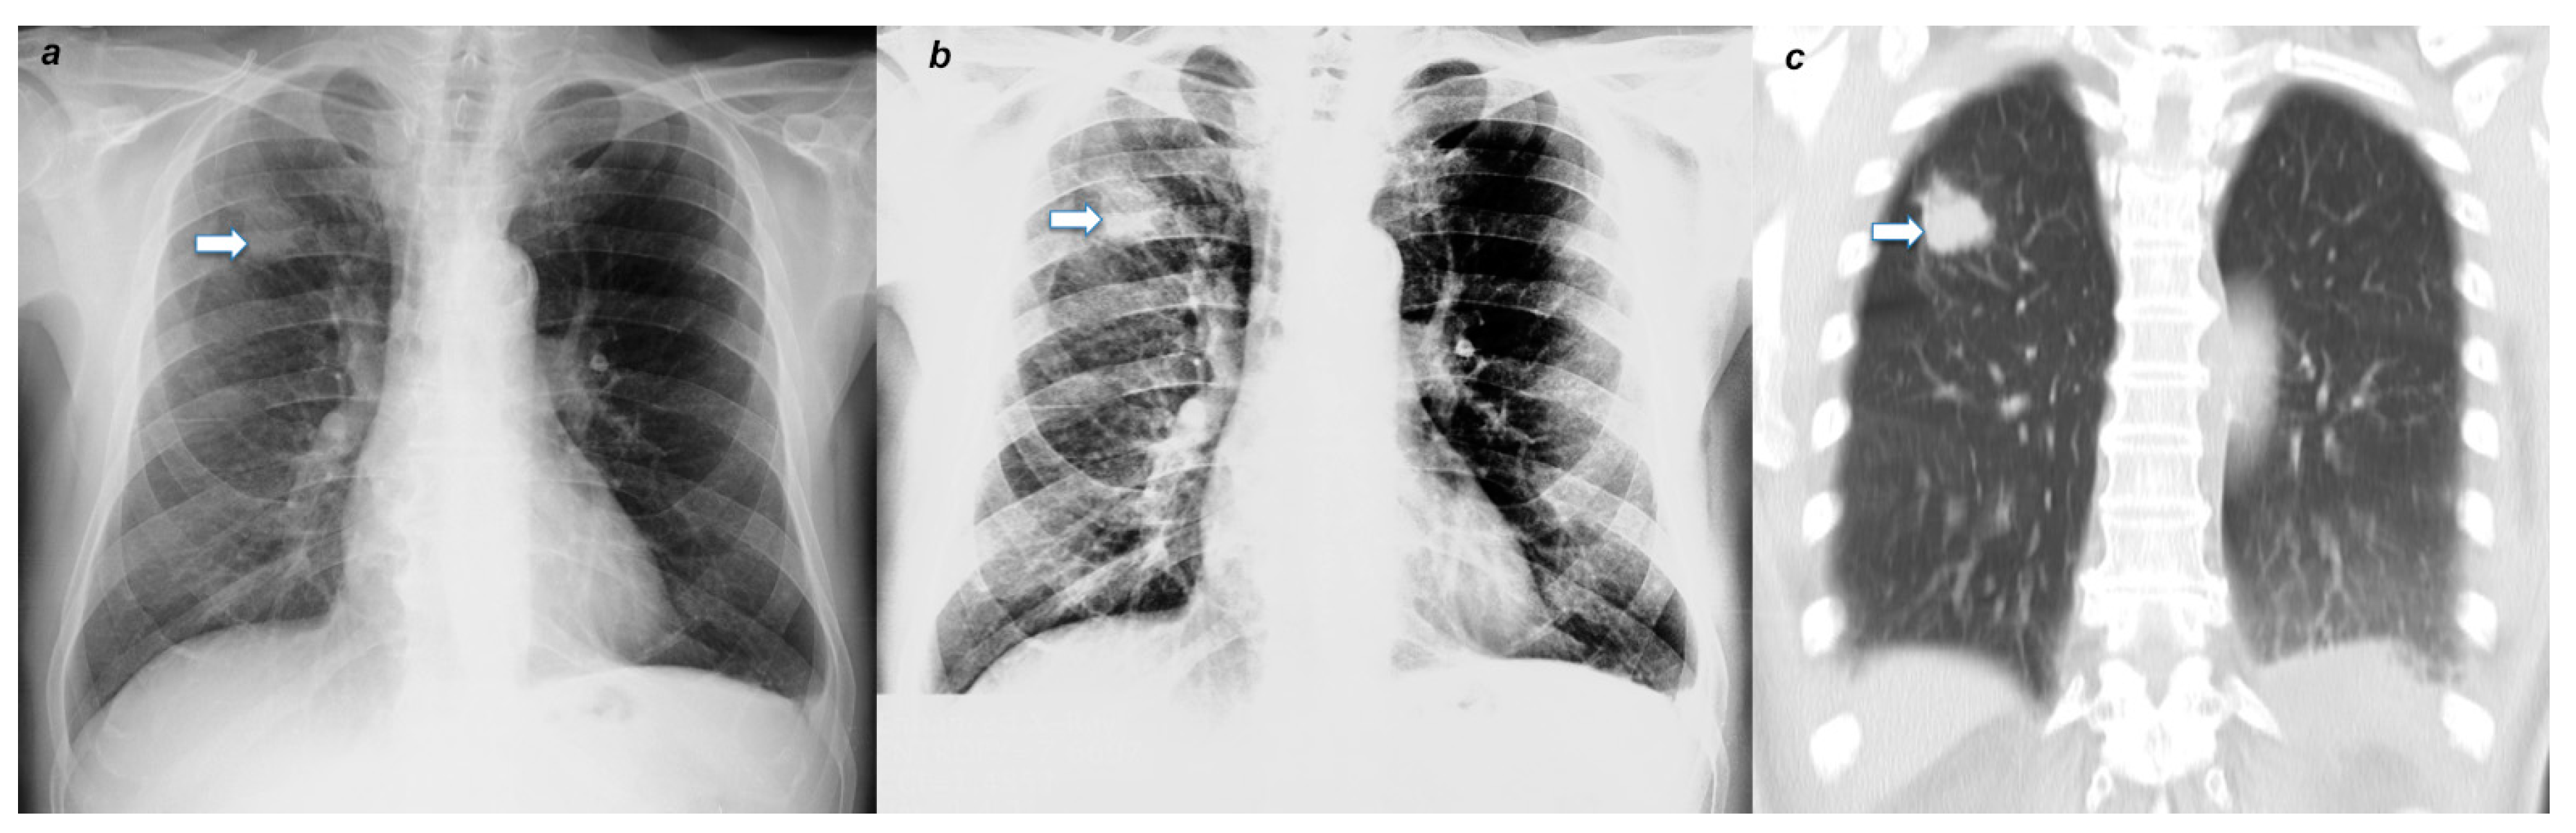

4.2. Radiological Evaluation and Statistics